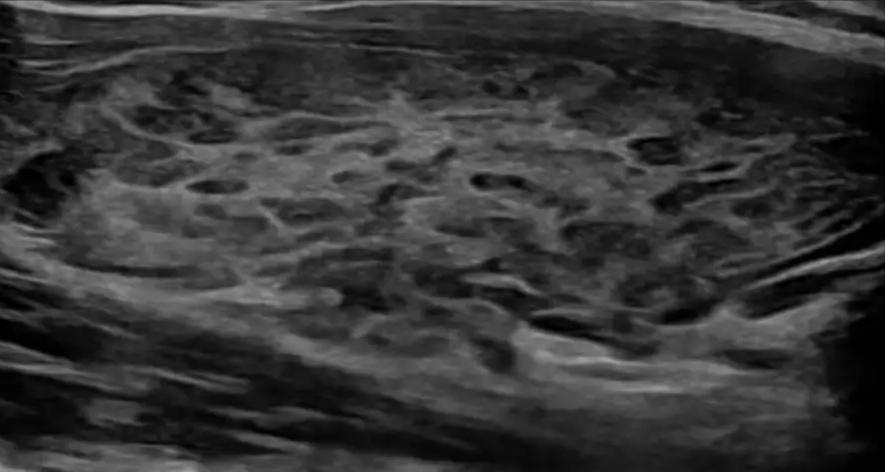

桥本背景下的弥漫性病变